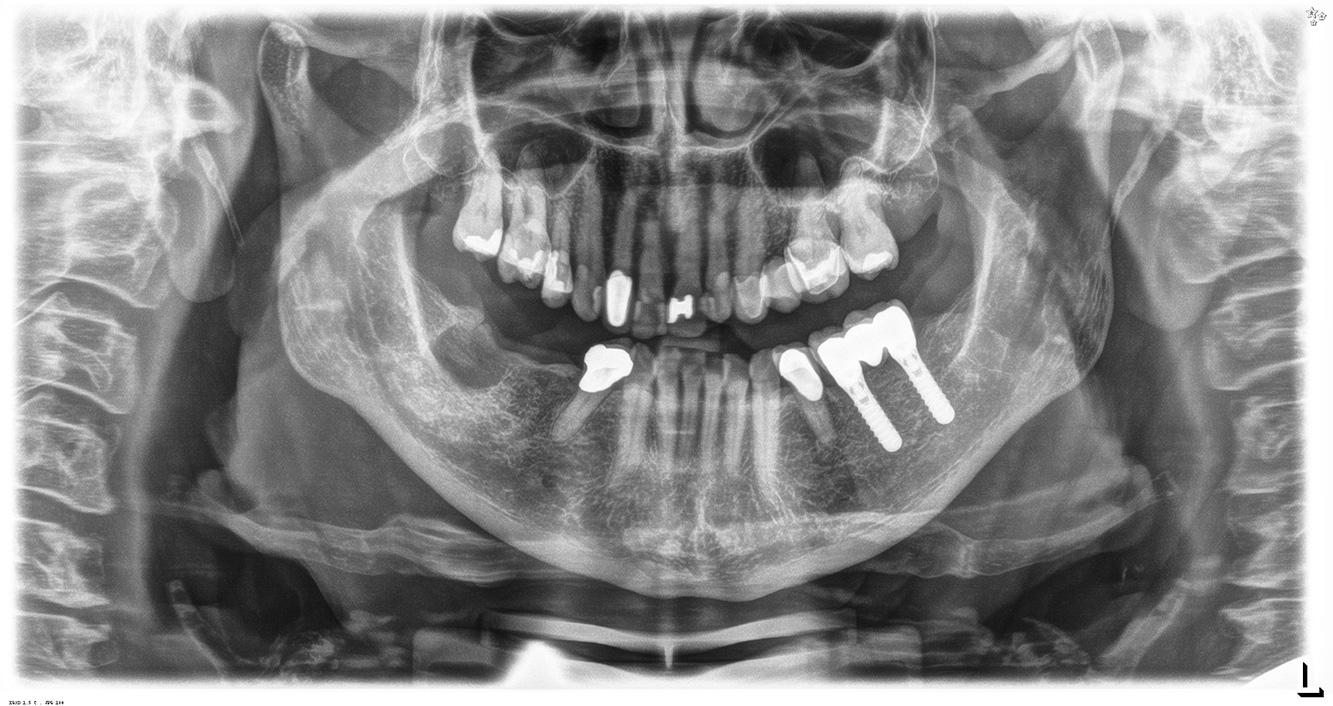

Die 68-jährige Patientin hat keine zahnmedizinisch relevanten allgemeingesundheitlichen Vorerkrankungen oder Medikation, auch aus dem Lebensstil ergibt sich kein besonderes Risiko. Die Patientin hat zwei Implantate (3. Quadrant, seit fünf Jahren) sowie eine parodontale Vorerkrankung (Parodontitis Stadium IV, Grad B) mit Zahnverlust. Derzeit zeigen sich stabile parodontale Verhältnisse, jedoch erhöht Parodontitis maßgeblich die biologischen Komplikationen bei Implantationen und es droht der Implantatverlust (21).

Da die Patientin keine besonderen Risikofaktoren mit spezifischen zahnmedizinischen Auswirkungen hat, ist der aus der Mundgesundheit ermittelte Bedarf maßgebend. Hier ist einmal jährlich ein ausführlicher Parodontalstatus empfohlen. So kann rechtzeitig auf eine mögliche Progression der parodontalen Vorerkrankung oder die Entstehung einer Periimplantitis reagiert werden.

Aufgrund der Implantatsituation mit parodontaler Vorerkrankung hat die Patientin ein Entstehungsrisiko für eine Periimplantitis – empfohlen wird eine Wiedervorstellung im Intervall von drei bis vier Monaten.